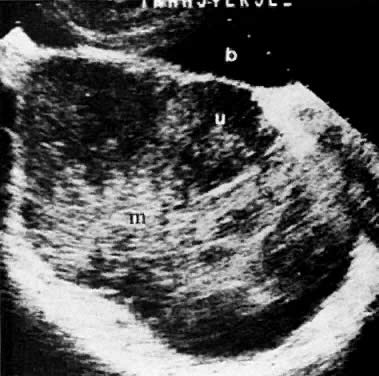

In locally confined disease, a cervical mass may be seen by ultrasound (Fig. 5B and C). In locally advanced disease, the cervix may become diffusely enlarged, inhomogeneous, and irregularly marginated (Fig. 6A and B).

Fig. 6. Advanced cervical carcinoma. Sagittal ( A) and transverse ( B) sonograms of the pelvis show a markedly enlarged, irregular cervical mass invading both parametria ( black arrows ), encasing the right ureter laterally, and obliterating the fat planes ( white arrows) between the cervix and bladder anteriorly, and cervix and rectum posteriorly. The mass is obstructing the uterus, causing hydrometras. Sagittal sonogram ( C) of the right kidney shows moderate hydronephrosis. ( c, cervical mass; ur, ureter; b, bladder; h, hydrometras; k, kidney.)